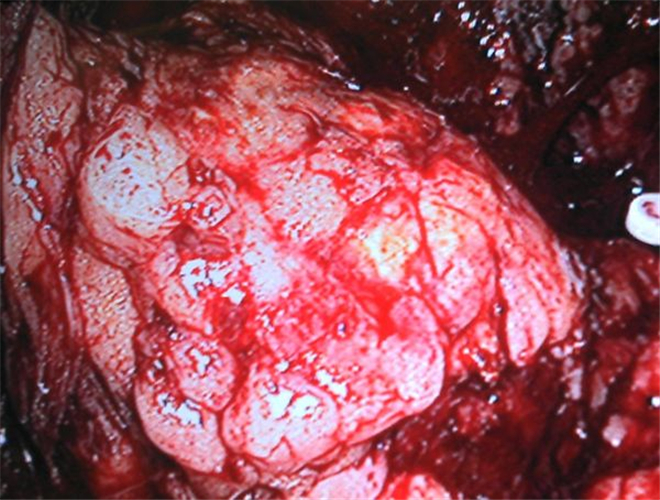

摘除的腎上腺腫瘤

已切除的腎上腺腫瘤

手術中看到的腎上腺腫瘤

微創切除的腎上腺腫瘤